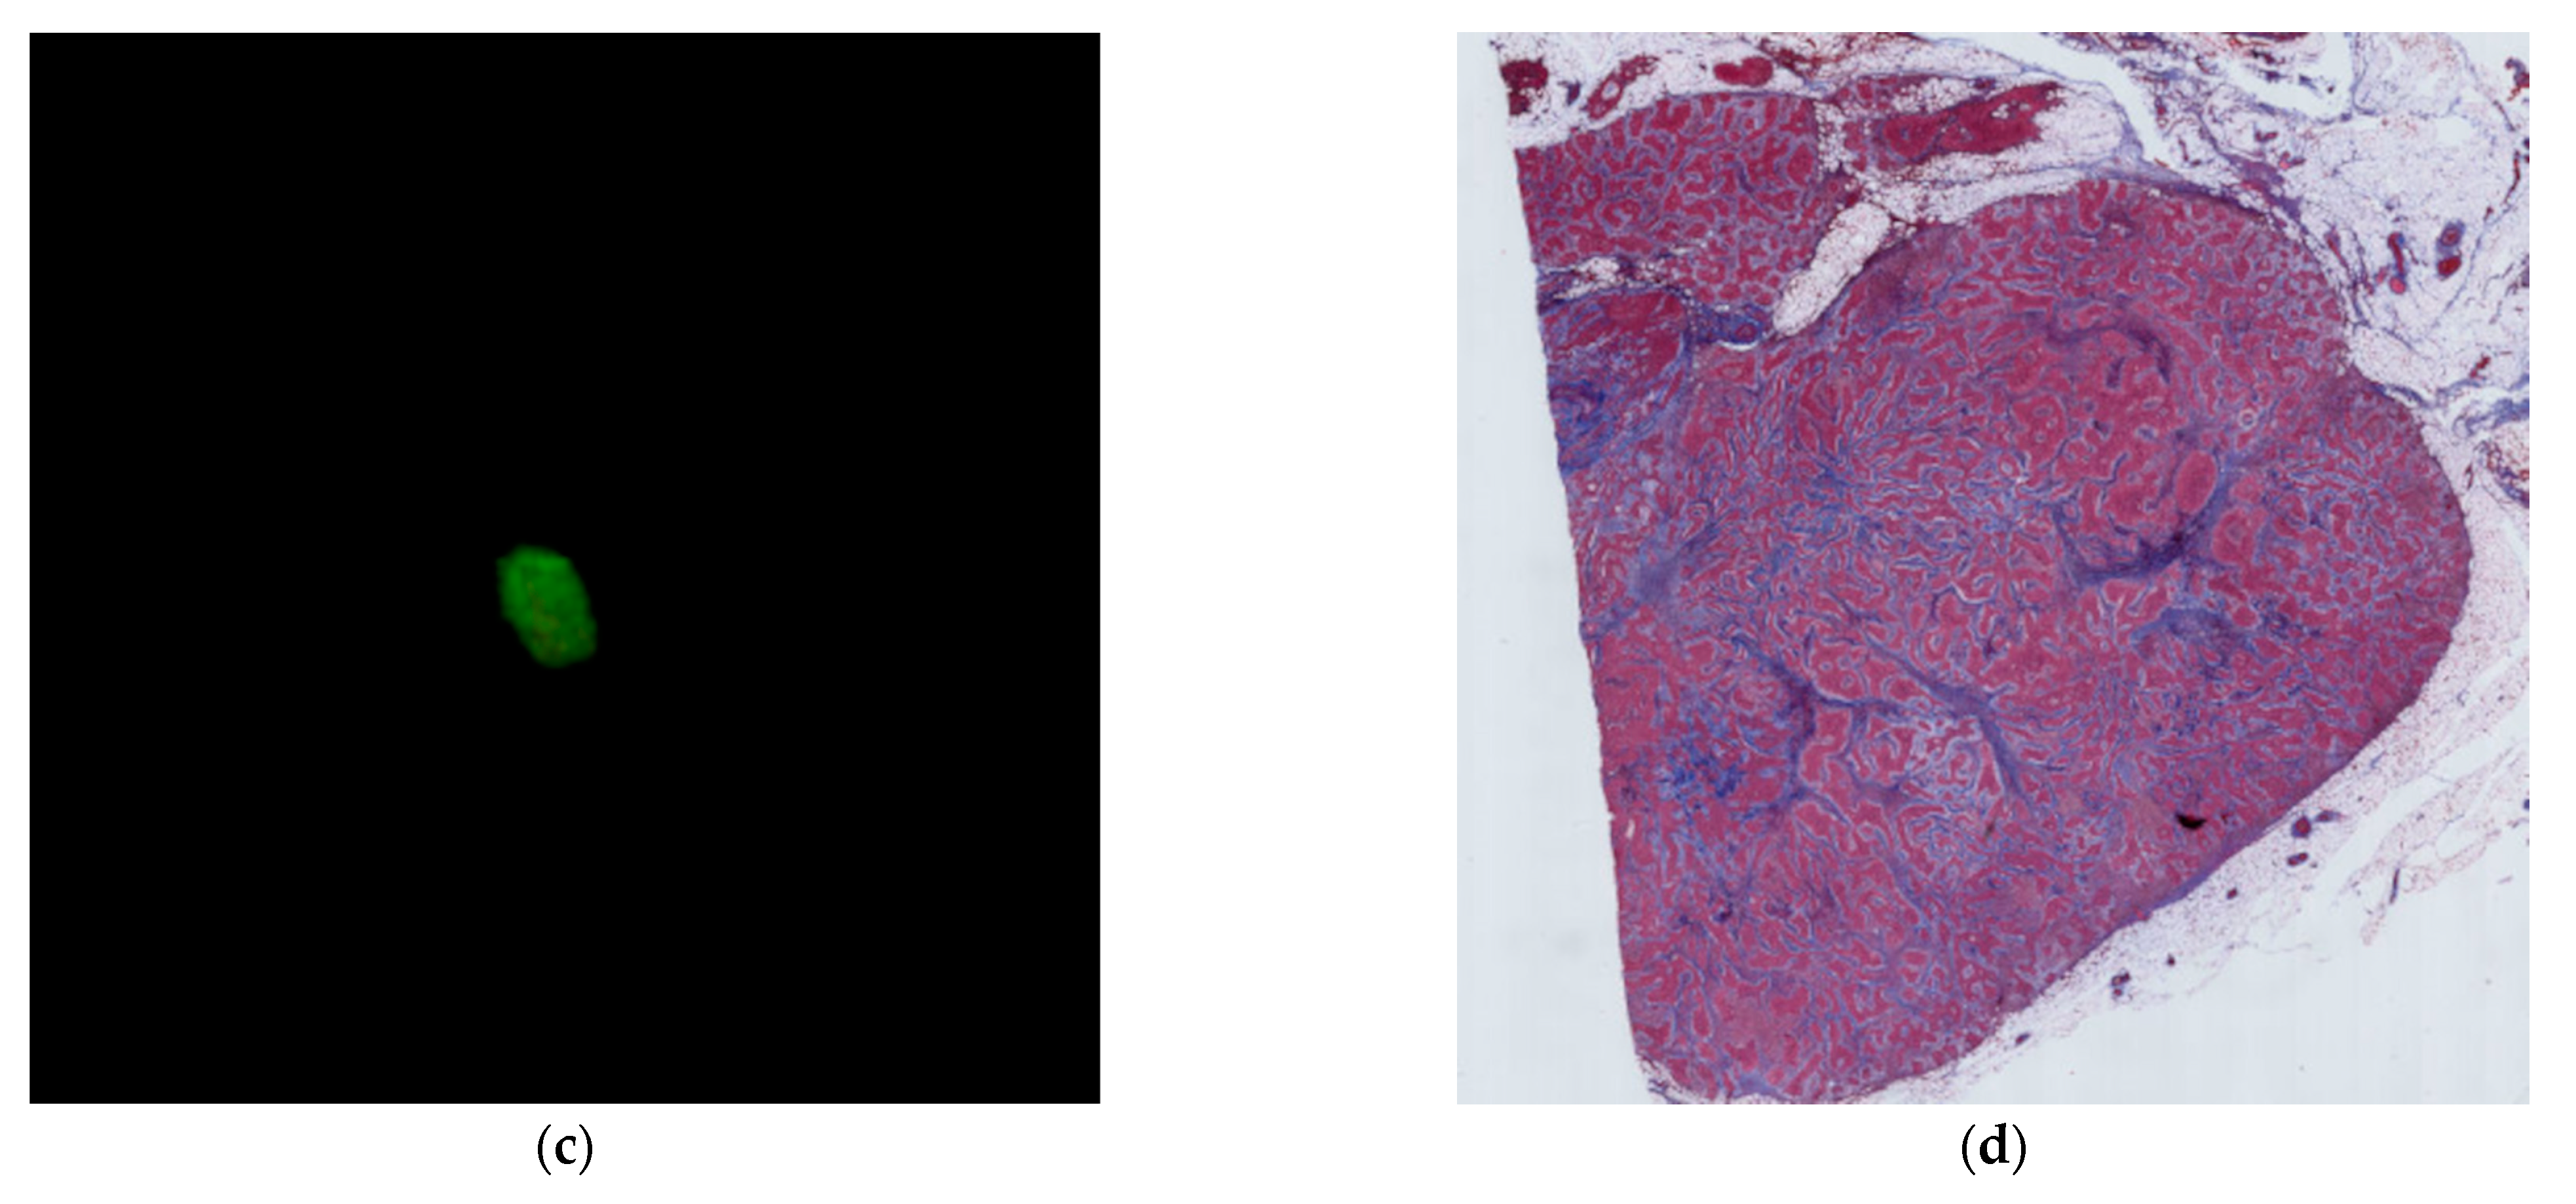

2.3. Image Analysis

2.4. Histological Evaluation